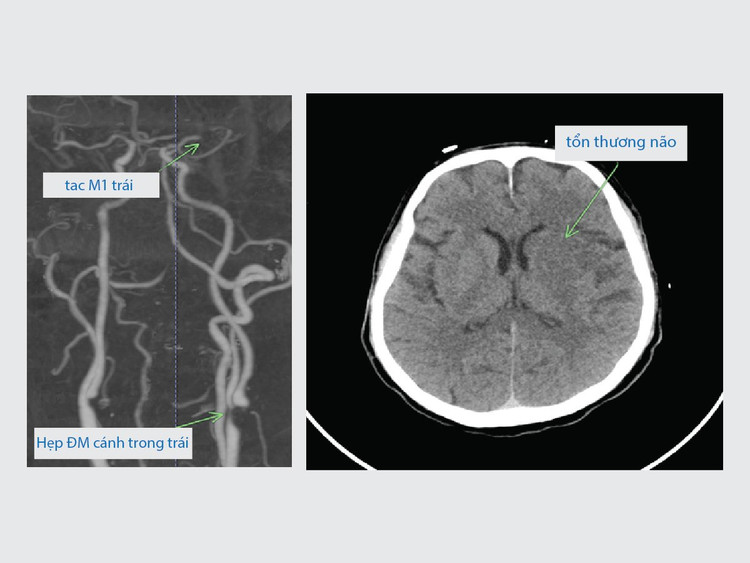

| Phim chụp hẹp động mạch cảnh trong bên trái và tắc động mạch não giữa trái của người bệnh lúc mới vào viện |

Ngay khi vào Khoa Cấp cứu và Điều trị tích cực Thần kinh – Đột quỵ, người bệnh được các bác sĩ chỉ định chụp CT 128 dãy, kết quả có hình ảnh hẹp động mạch cảnh trong trái, tắc động mạch não giữa bên trái. Đánh giá ban đầu cho thấy tình trạng người bệnh nặng, nếu không được can thiệp thì nguy cơ để lại di chứng nặng nề nên các bác sĩ đã chỉ định can thiệp mạch lấy huyết khối, tái thông hoàn toàn mạch não cho người bệnh.